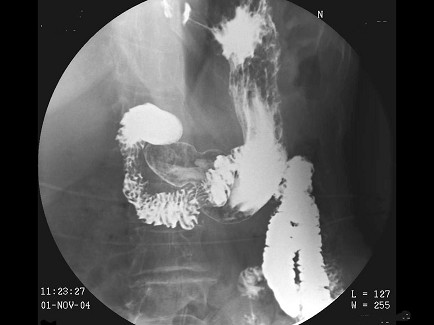

女,74岁,上腹痛4月,纳差,结合图像,最可能的诊断为()

A.正常表现

B.胃炎

C.胃癌

D.笔杆征

E.十二指肠占位